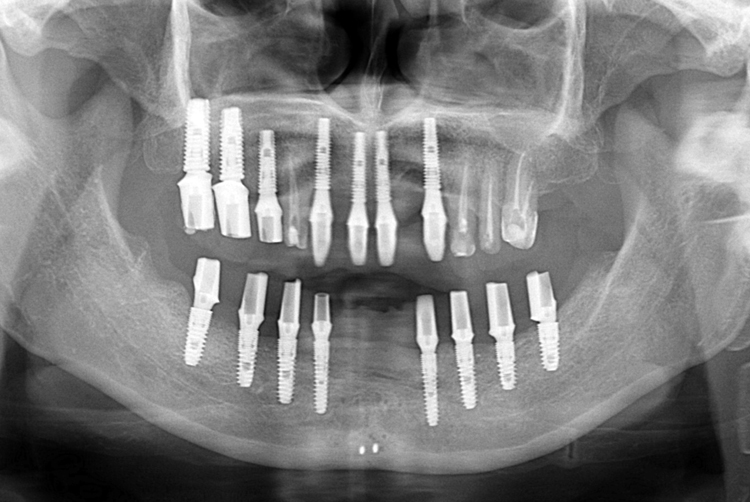

치료사례

세종치과의 진심 어린 치료는 결과로 말합니다.

실제 내원하신 환자분들의 치료 전·후 사례를 확인해보세요.

모든 치료사례 전후사진은 환자분의 동의하에 촬영되었습니다.

모든사진은 동일 환자분의 전후모습을 촬영하였으며, 사진의 밝기조절 외에 임의 수정이 없음을 알려드립니다.